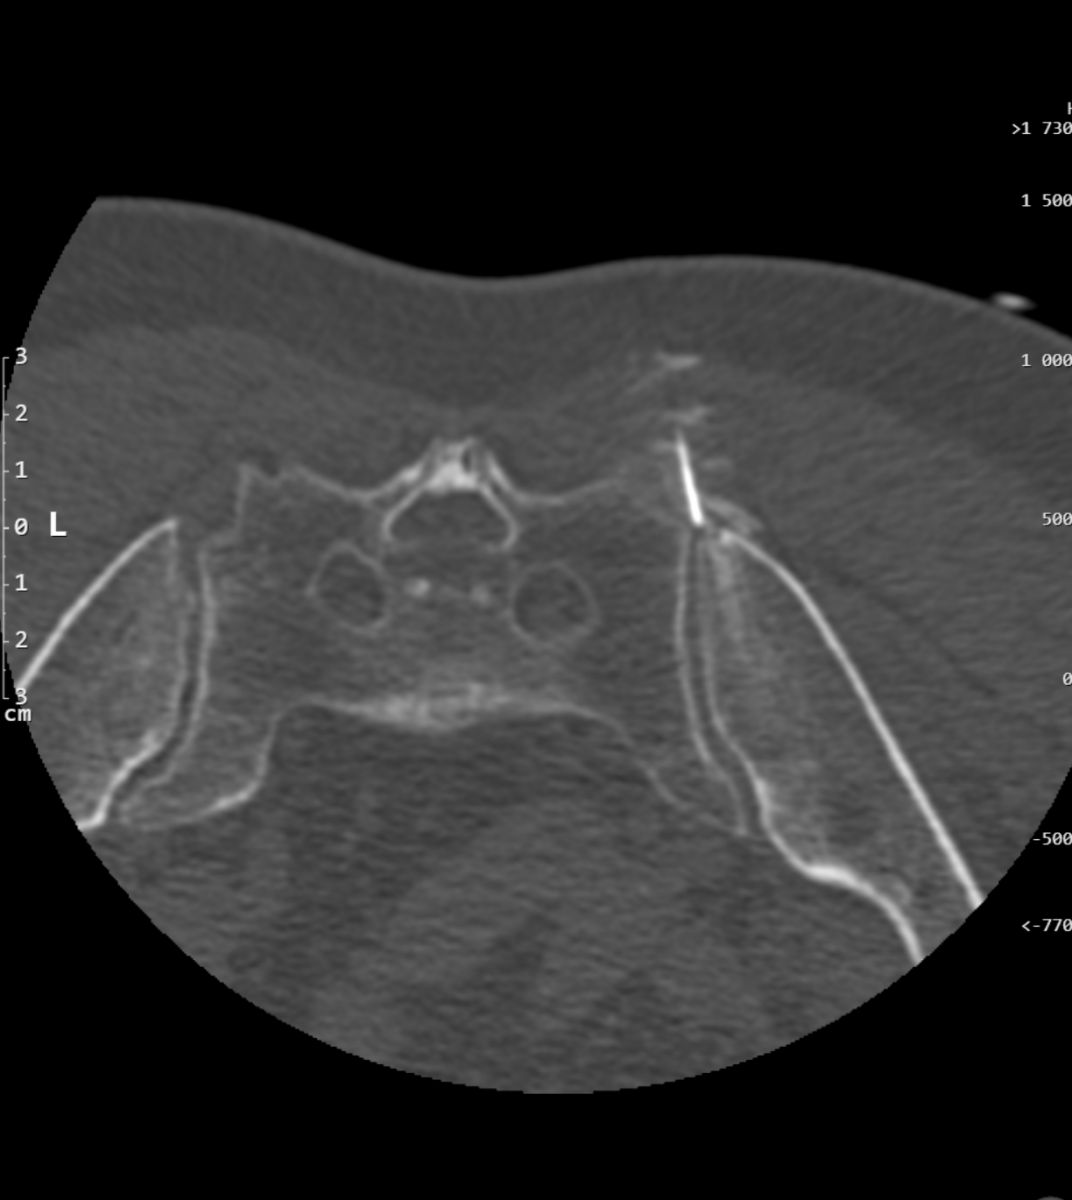

Co se vlastně při CHLSE odehrává?

Při výkonu budete ležet na břiše, a nebudete se hýbat, celý výkon trvá většinou 15 – 20 minut, výjimečně déle. Zezadu lékař zavede tenkou jehlu (tenčí než na odběr krve) do místa, kde probíhají kmeny sympatického nervstva (vedle páteře) a injektuje léčebnou směs sestávající z alkoholu, anestetika a malého množství kontrastní látky, celkové množství směsi je okolo 13 ml. Aplikace směsi může být spojena s nepříjemnými zážitky – většinou bolestmi do břicha či do zad, též se můžete celkově potit. Poté, co je směs umístěna, lékař vytáhne jehlu a místo přelepí.